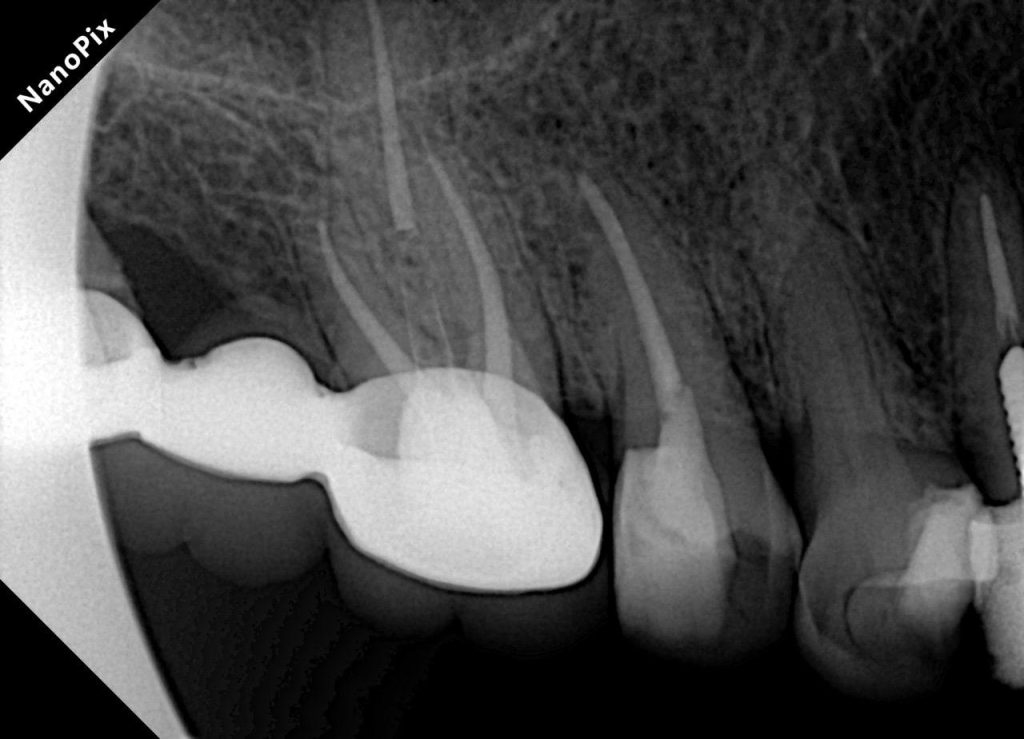

Radiographic Findings

- Previous endodontic treatment visible in UL3 and UL6

- Inadequate obturation and coronal leakage

- Widened PDL space on UL6

- Normal apical architecture on other teeth

- No sinus tract present

FIVE-YEAR FOLLOW-UP

At 5 years:

- Tooth structure remained intact

- Prosthetic margins were stable

- Periapical radiographic healing was evident

- Patient remained asymptomatic

- Excellent gingival response observed

- No secondary caries or debonding

- Occlusion stable and functional

✅ Long-term quadrant stability achieved